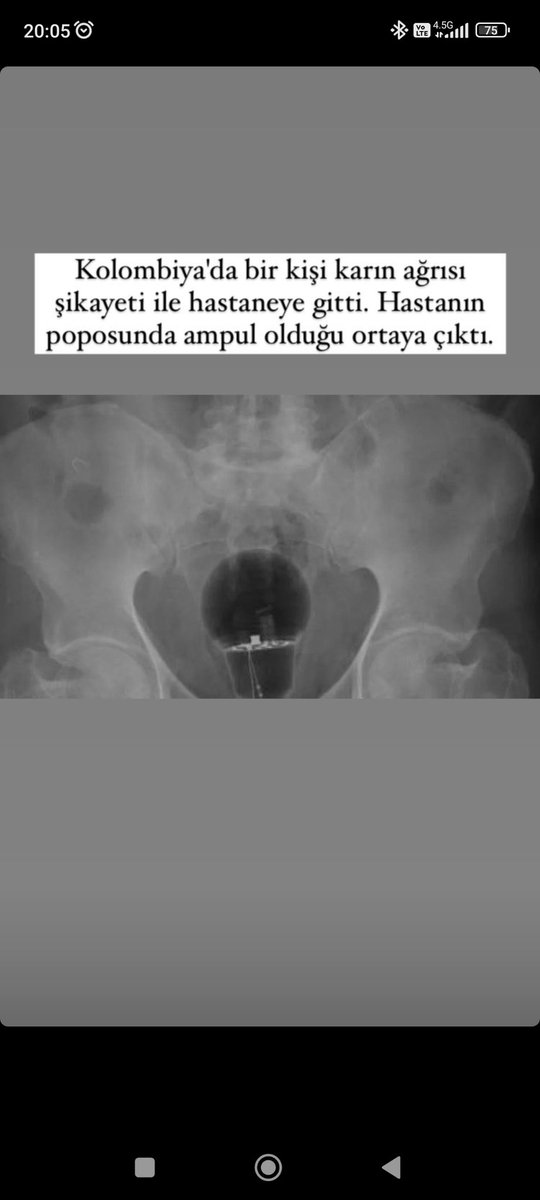

ulan bu ok zehirli işte bu atmayın artık yaaa